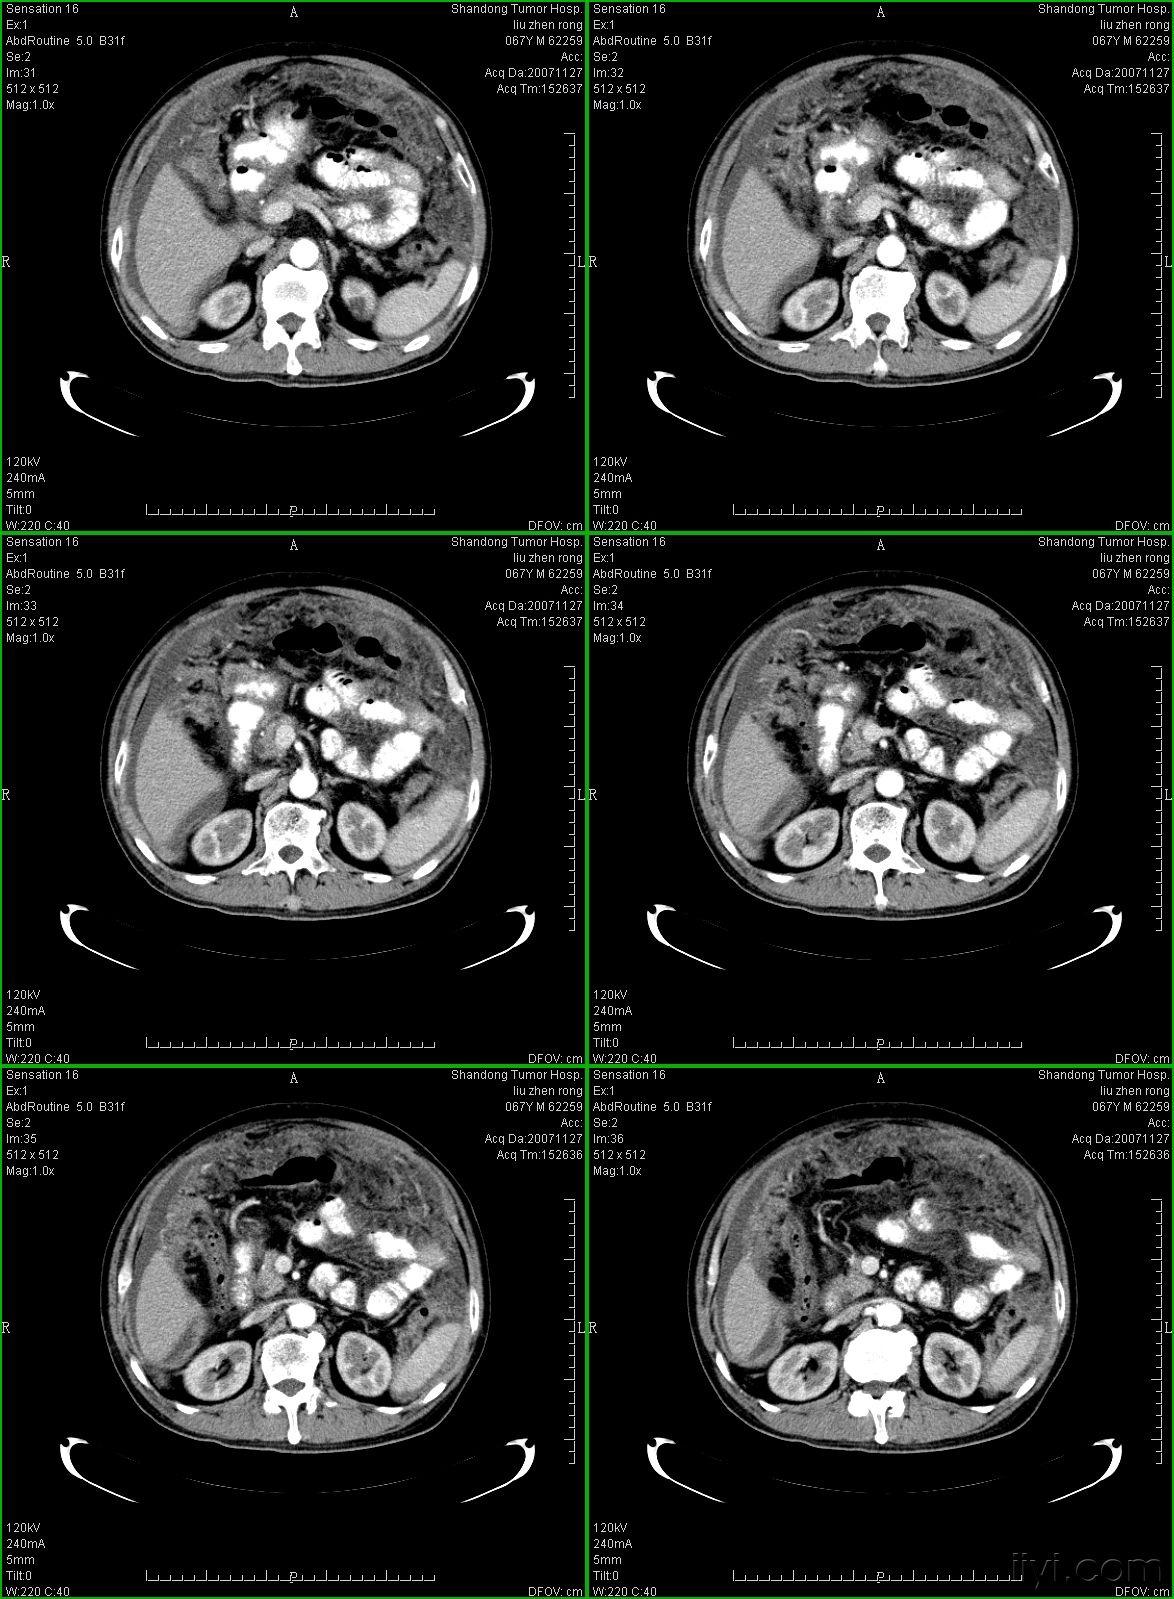

典型的大网膜,肠系膜转移瘤,很经典

典型的大网膜肠系膜转移瘤很经典